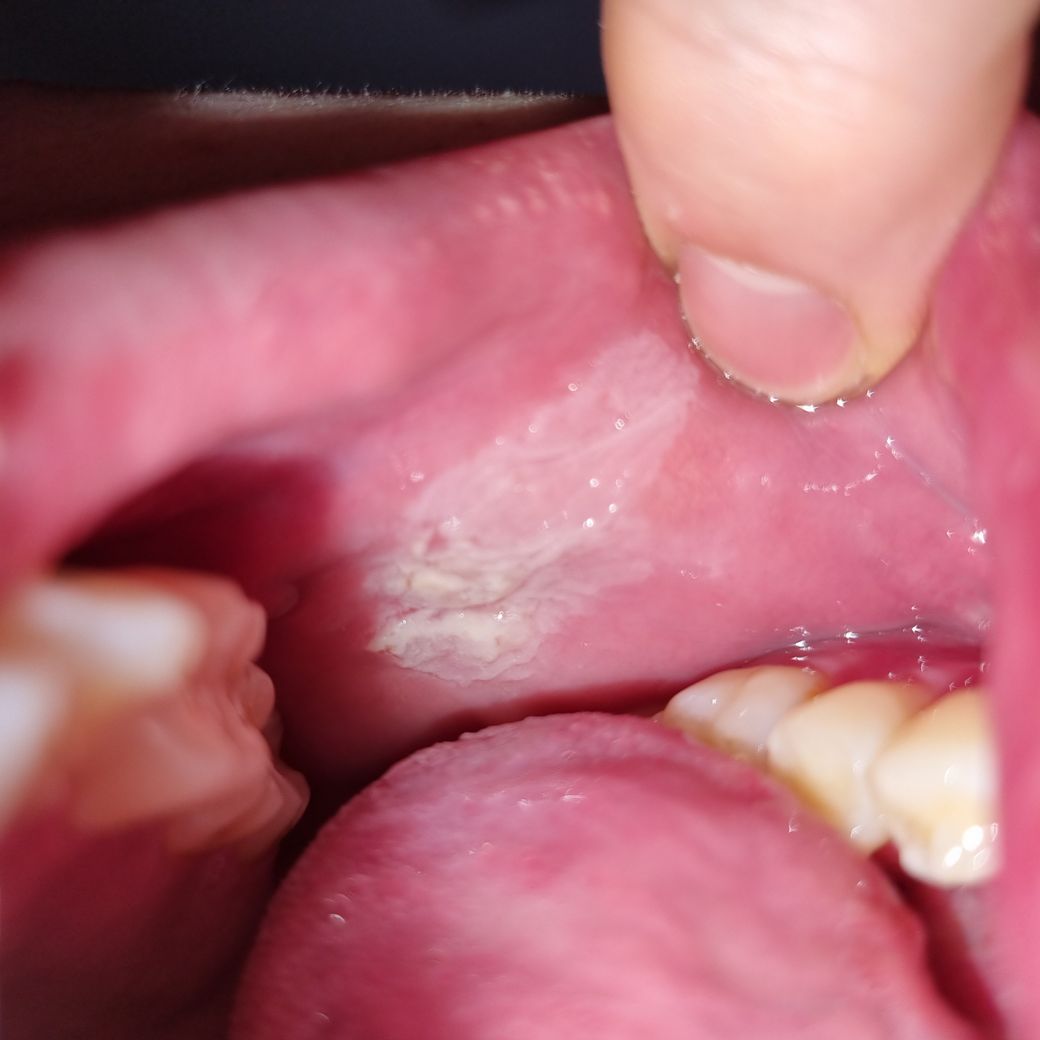

입 안쪽에 하얗게 막이생겼는데 뭘까요?

어제부터 입 벽이 오돌토돌해서 확인해보니 하얗게 막이생겨있네요ㅠ 병원을 가봐야할까요?

이렇게 되어있습니다...!

백색증으로 보이며 2주간에 없어지지 않으면 조직검사 받아보시는 것을 추천드립니다.

주기적이 경과관찰이 필요하며 크기가 커지거나 증상이 있을시 조직검사하여 수술이 필요할 수 있습니다.

어제 갑자기 생겼다고 하니 입안 볼점막에 생긴 구내염으로 추정됩니다.

사진상 볼점막외에 잇몸 부위도 약간 부어 있는 것으로 보입니다.

구강내 백색병소의 일종으로 보입니다.

백색병소는 보기에는 유사하나, 다양한 병소들이 보이는 특징이므로 이는 치과에 내원하셔서 검사를 받아보시는게 좋겠습니다.

치과 방문 후 검사가 필요해보입니다. 진균 감염에서부터 구강 내 연조직 질환이 의심되며 감별 진단을 해보아야 할 것으로 보입니다. 가까운 치과 방문 후 해당 부위에 대한 검사를 해보고 치료를 하셔야 할 것으로 보입니다. 단순히 외상으로 생긴 것이 아닌 감염으로 보여집니다.